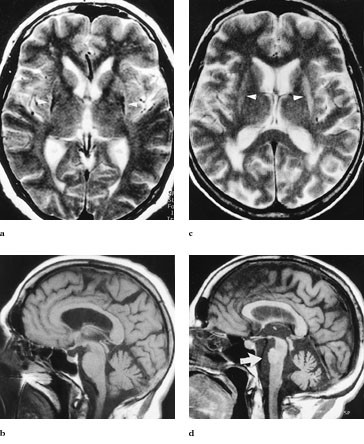

MR cerebrum viste lavsignalforandringer i putamen bilateralt med en hyperintens kant lateralt mot capsula externa og lett generell atrofi kortikalt og sentralt (fig 1a), mens cerebellum var normal (fig 1b). SPECT-undersøkelse med β -CIT viste nedsatt dopaminerg aktivitet i striatum bilateralt, mest uttalt i putamen og relativt symmetrisk (fig 2e). SPECT-undersøkelse med epideprid viste nedsatt D₂-reseptortetthet i putamen og nucleus caudatus bilateralt (fig 2f).

MR cerebrum viste høysignal lateralt og oppad i begge putamen (fig 1c) og markert (og økende) atrofi av cerebellare foliae, vermis cerebelli og av pons (fig 1d). I tillegg var det høysignalforandringer periventrikulært nær sideventriklenes bakhorn. SPECT-undersøkelse med β -CIT viste bilateral betydelig reduksjon av dopaminerg aktivitet, like mye i putamen og nucleus caudatus og mest på venstre side. SPECT-undersøkelse med epideprid var normal.

Ved striatonigral degenerasjon sees hyppig atrofi i putamen på T2-vektede bilder, atrofi kan også sees i globus pallidus med eventuelt nedsatt signal. Funn av en hyperintens kant på grensen mellom putamen og capsula externa, som hos pasient 1 og pasient 2 (fig 1a, 1c), er i to artikler funnet å ha høy spesifisitet for særlig striatonigral degenerasjon, mens atrofi og signalreduksjon i putamen alene er mer uspesifikt (6, 7). De mest typiske MR-funnene for sporadisk olivopontocerebellar atrofi er atrofi av cerebellum og pons relativt tidlig i forløpet, som hos pasient 2 (fig 1d) (6). Normal MR-undersøkelse er observert hos opptil 20 % av pasienter med multippel systematrofi (8). Ved Parkinsons sykdom påvises ikke patologiske forandringer ved MR hyppigere enn hos friske kontrollpersoner, og funnene er da av uspesifikk natur.

Ved progressiv supranukleær parese er følgende MR-funn de mest karakteristiske: Redusert anteroposteriør diameter av mesencephalon (<1,7 cm), signaløkning i mesencephalon, dilatasjon av tredje ventrikkel og frontal- og temporallappsatrofi (6). Ingen av våre pasienter hadde slike funn ved MR.